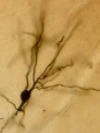

Señale lo correspondiente a la imagen: a) Carcinoma espinocelular. b) Melanoma. c) Queratosis actínica. d) Carcinoma basocelular. Señale lo correspondiente a la imagen: a) Carcinoma basocelular. b) Carcinoma espinocelular. c) Angioma. d) Melanoma amenalocítico. Señale lo correspondiente a la imagen: a) Carcinoma espinocelular. b) Nevus atípico. c) Melanoma amelanocítico. d) Úlcera de Marjolin. Señale lo correspondiente a la imagen: a) Carcinoma espinocelular. b) Queratosis seborreica. c) Nevus atípico. d) Melanoma. Señale lo correspondiente a la imagen: a) Hematoma ungueal. b) Carcinoma espinocelular. c) Melanoma ungueal. d) Nevus melanocitico. Señale lo correspondiente a la imagen: a) Melanoma anal. b) Hemorroides. c) Carcinoma espinocelular. d) Ninguna es correcta. Señale lo correspondiente a la imagen: a) Nevus atípico. b) Melanoma in situ. c) Nevus melanocítico. d) Angioma. Señale lo correspondiente a la imagen: a) Melanoma. b) Carcinoma espinocelular. c) Queratosis actínica. d) Carcinoma basocelular. Señale lo correspondiente a la imagen: a) Angioma. b) Melanoma in situ. c) Carcinoma basocelular. d) Lago venoso. Señale lo correspondiente a la imagen: a) Carcinoma espinocelular. b) Infección por candida. c) Leucoplasia. d) Carcinoma basocelular. Señale lo correspondiente a la imagen: a) Úlcera. b) Nevus atípico. c) Nevus melanocítico. d) Melanoma. Señale lo correspondiente a la imagen: a) Lago venoso. b) Melanoma. c) Nevus melanocítico. d) Carcinoma espinocelular. Señale lo correspondiente a la imagen: a) Melanoma. b). c). d) Nevus melanocítico. Señale lo correspondiente a la imagen: a) Ambas máculas son nevus atípicos. b) La imagen de arriba es un nevus típico. c) Ambas máculas son nevus típicos. d) La imagen inferior muestra un melanoma in situ. Señale lo correspondiente a la imagen: a) Angioma. b) Carcinoma basocelular. c) Nevus atípico. d) Melanoma amelanocítico. Señale lo correspondiente a la imagen: a. b. Señale lo correspondiente a la imagen: a. b. Señale lo correspondiente a la imagen: a. b. Señale lo correspondiente a la imagen: a. b. Señale lo correspondiente a la imagen: a. b. Señale lo correspondiente a la imagen: a. b. Señale lo correspondiente a la imagen: A. b. Señale lo correspondiente a la imagen: a. b. Señale lo correspondiente a la imagen: a. b. Señale lo correspondiente a la imagen: a. b. Señale lo correspondiente a la imagen: a) Tumor primario de estirpe melanocítica. b) Carcinomas espinocelulares múltiples. |